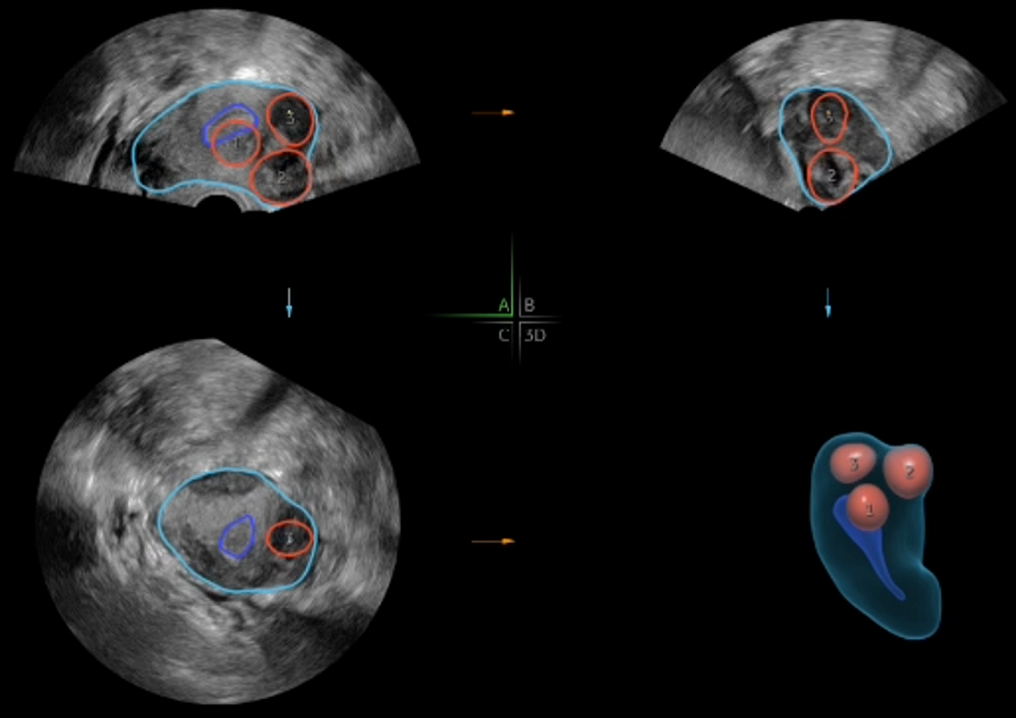

6. Otomatik Folikül Takibi (S-AVC)

AI destekli 3D boyutlu ultrasonografi cihazları sayesinde uterusa ait doğuştan gelen ya da sonradan kazanılmış anomalilerin tanımlanması ve bu patolojilerin rahim içerisine olan etkisi kolaylıkla daha ileri görüntüleme yöntemleri kullanılmadan inceleme yapılmaktadır.

Embriyoloji laboratuvarımızda, yapay zekâ destekli sistemler sayesinde embriyo ve yumurta hücreleri (oosit) değerlendirilmekte, en uygun sperm seçimi yapılmaktadır. Kliniğimizde ise 3D ve yapay zekâ destekli ultrason cihazları ile folikül takibinin yanı sıra miyom, polip ve uterin anomalileri de yüksek hassasiyetle tanımlanmaktadır.